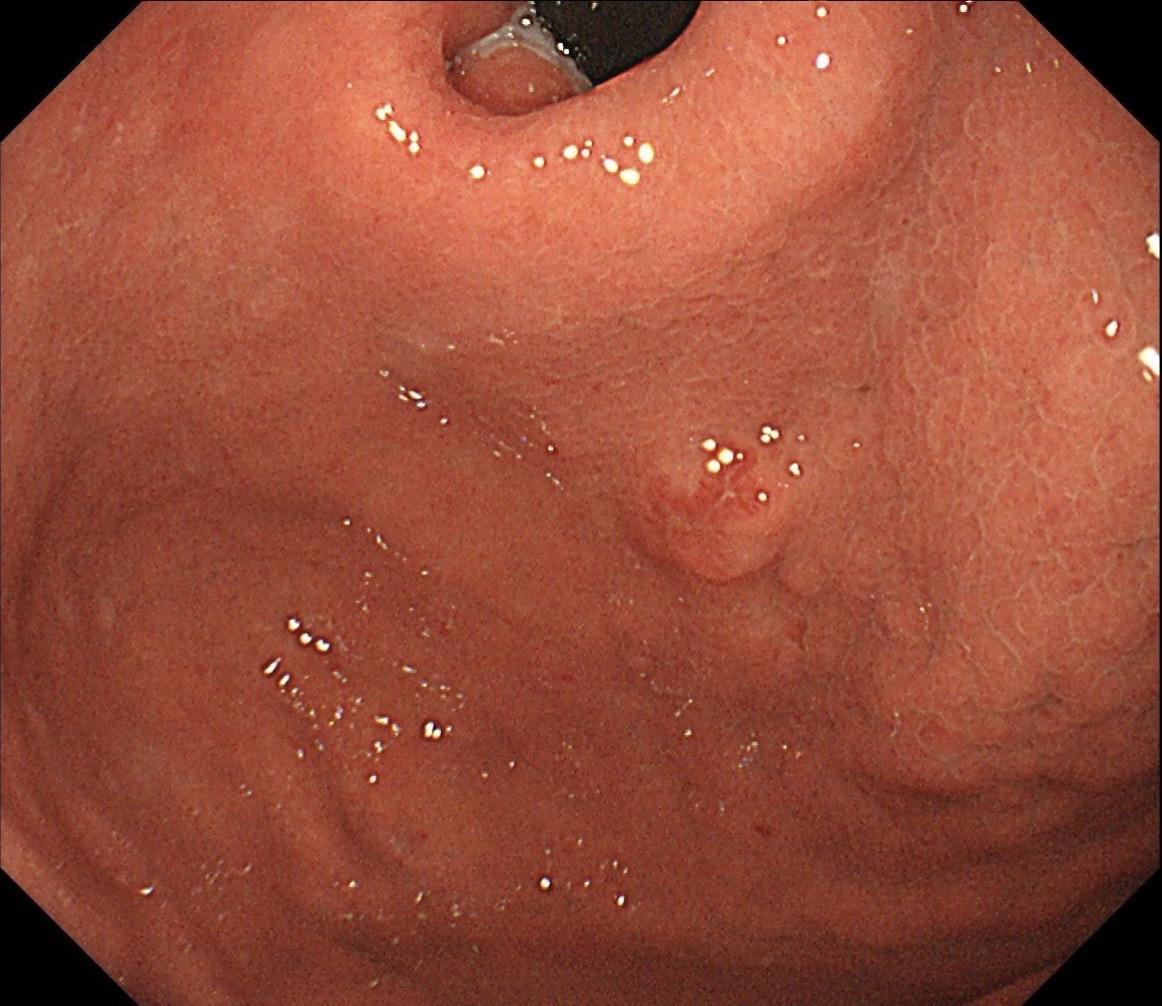

小小的糜烂一枚。这样的病灶,就算结果是阴性的,也很有意义~

2025-12-11 22:46